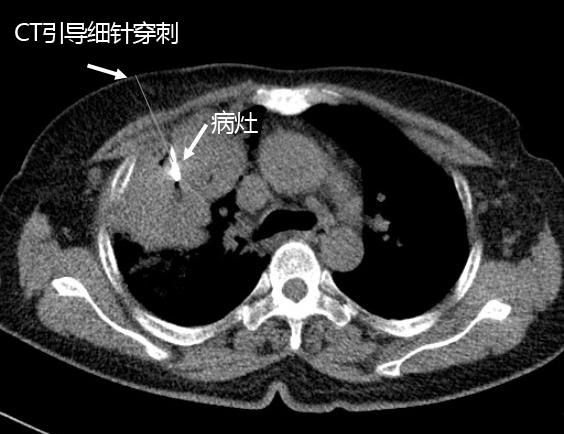

康美醫院開展經皮肺細針穿刺活檢術 ——診斷周圍型肺癌的金标準

發布時間:2018-01-22 閱讀:4137 患者劉某,女,62歲,因“發現頸部淋巴結腫大2月餘”于本月6日入院。檢查雙側頸部可扪及多個大小約1*0.5cm淋巴結,質硬,無壓痛。入院後經胸部CT增強平掃發現右肺上葉腫塊,結合腫瘤标志物檢測,考慮肺癌。

通過病理檢查結果确診爲右肺腺癌,李主任随即根據該型肺癌特點結合患者身體情況,爲其制定個性化治療方案,爲患者争取到了寶貴的治療時機,取得良好治療效果。